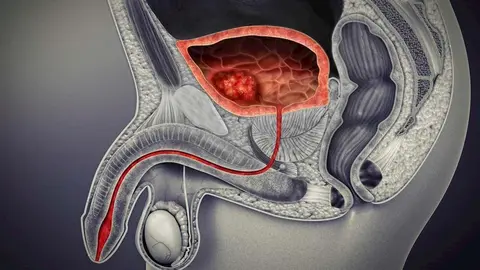

Presentan un prometedor estudio de cáncer de vejiga

Un estudio revela que el camino es la personalización de los tratamientos de cáncer vejiga y el descubrimiento de nuevos biomarcadores